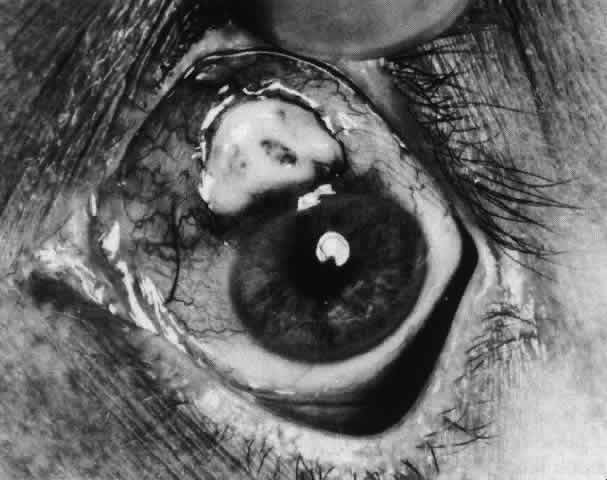

of the eye. A posterior scleritis often occurs as an extension of anterior

disease; but, as in Figure 20, most of the inflammation (in some cases all of the inflammation) is in

the posterior segment and the exudative detachments and subretinal granulomas

can be mistaken for malignant melanoma.  Fig. 19. Anterior necrotizing scleritis. The eye was removed because of loss of

Fig. 20. Posterior scleritis. This eye was removed because of loss of vision and

pain, mistakenly diagnosed as malignant melanoma. (Courtesy of Professor N. Ashton) Fig. 20. Posterior scleritis. This eye was removed because of loss of vision and

pain, mistakenly diagnosed as malignant melanoma. (Courtesy of Professor N. Ashton)

|